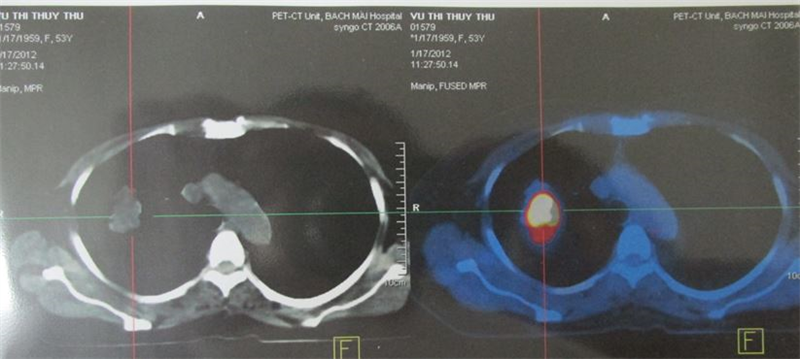

+ Bệnh nhân được chỉ định PET/CT

Hình 3,4,5: Hình ảnh PET/CT u phổi P kích thước 3,4cm tăng hấp thu FDG, max SUV là 7,8, di căn xương cột sống, xương chậu trái max SUV là 8,4.